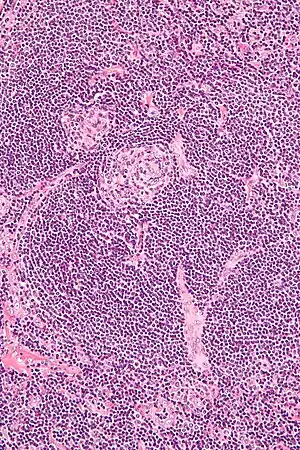

Micrograph of Castleman disease showing hyaline vascular features including atrophic germinal center, expanded mantle zone, and a radially penetrating sclerotic blood vessel ("lollipop" sign). H&E stain.

• Hyaline vascular: regressed germinal centers, follicular dendritic cell prominence or dysplasia, hypervascularity in interfollicular regions, sclerotic vessels, prominent mantle zones with an "onion-skin" appearance.[14]